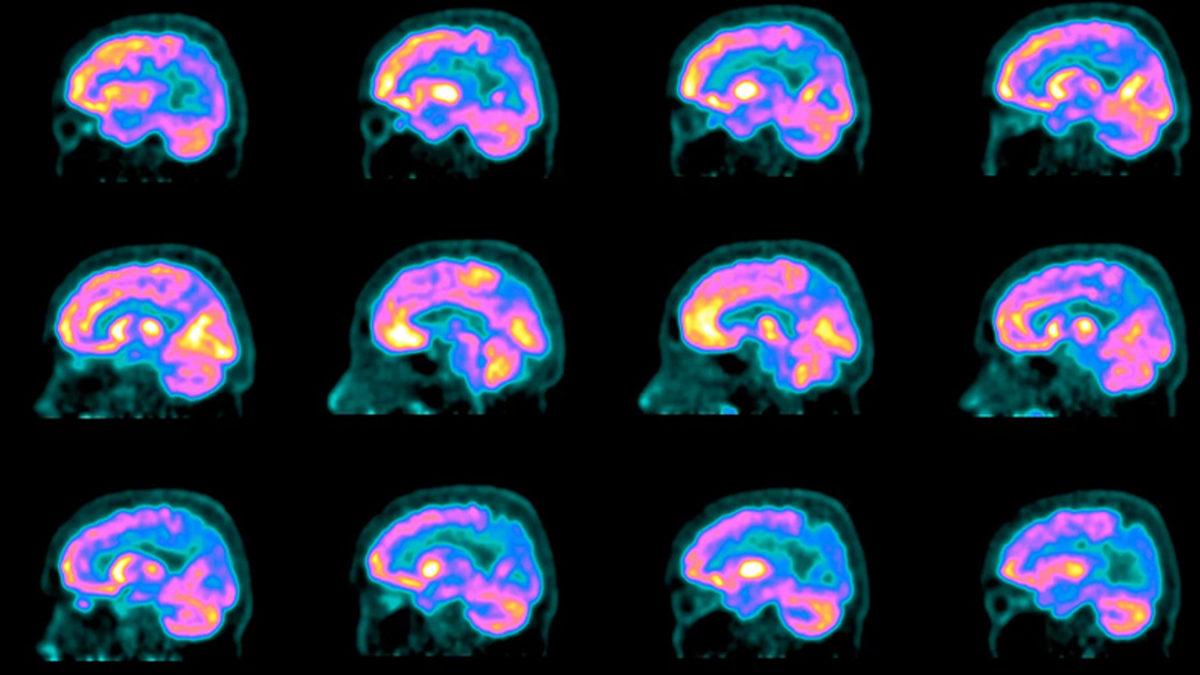

Yeni teknikler, Alzheimer'ı ölümden önce teşhis etmeyi mümkün kılıyor. MR gibi görüntüleme testleri, hafıza kaybının diğer nedenlerini dışlayabilir. Özel PET taramaları beta-amiloid plakları ve tau proteinlerini tespit edebilir.